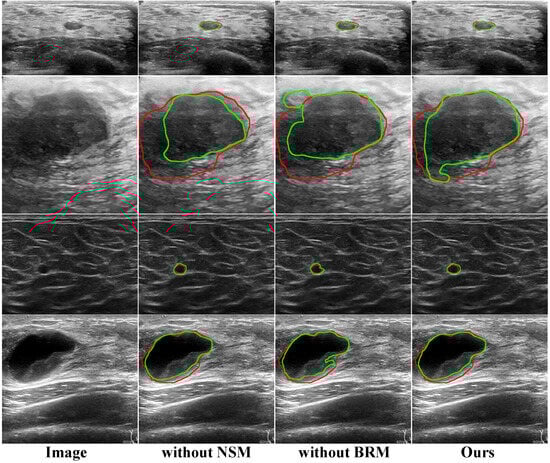

The visualization of our method and comparative methods on the BUSI dataset and Dataset B is shown in Figure 6. Our method has the best performance in segmenting tumors. For instance, in the case of blurred tumor boundaries (first row and third row), other methods exhibit significant instances of false negatives, while our method addresses this issue well. Specifically, the reason lies in the BRM’s ability to extract complementary regions and details of tumors and enhance the saliency analysis of intermediate features through the attention mechanism, enabling increased focus on object regions. Similarly, under speckle noise (second row and fourth row) conditions, NSBR-Net exhibits no issues with false positives.

To further validate the boundary refinement capability of BRM, we present the visualization of ablative experiment results in Figure 7. We selected tumors of varying sizes for analysis, with the first and third rows representing small tumors and the second and fourth rows representing large tumors. It can be observed that regardless of the size of the tumor, the segmentation results of the model incorporating BRM (second and fourth columns) are better fitted compared to those without BRM (third column). This further confirms that BRM indeed refines the boundary segmentation results, enabling more accurate localization of lesion boundaries, which is crucial for clinical applications.

Figure 6. Qualitative comparison of different methods on BUSI [19] (first row and second row) and Dataset B [21] (third row and fourth row). The red curve is the ground truth boundary. The green curve is the segmentation results of these methods.

Figure 7. Visualization results of the ablative experiment on BUSI [19] (first row and second row) and Dataset B [21] (third row and fourth row). The red curve is the ground truth boundary. The green curve is the segmentation results of different components.